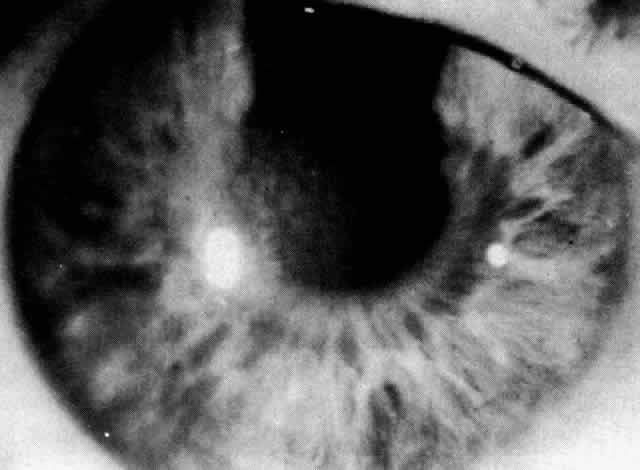

The most common findings are the maplike opacities (Figs. 1 AND 2), which can be detected by wide oblique illumination.8 The dot changes (Fig. 3) are seen by direct illumination, and fingerprint lines (Fig. 4) often need indirect illumination from the iris or retroillumination for detection. The distribution of the lesions can change over time.

Fig. 4. Epithelial basement dystrophy: fingerprint lines shown in retroillumination.